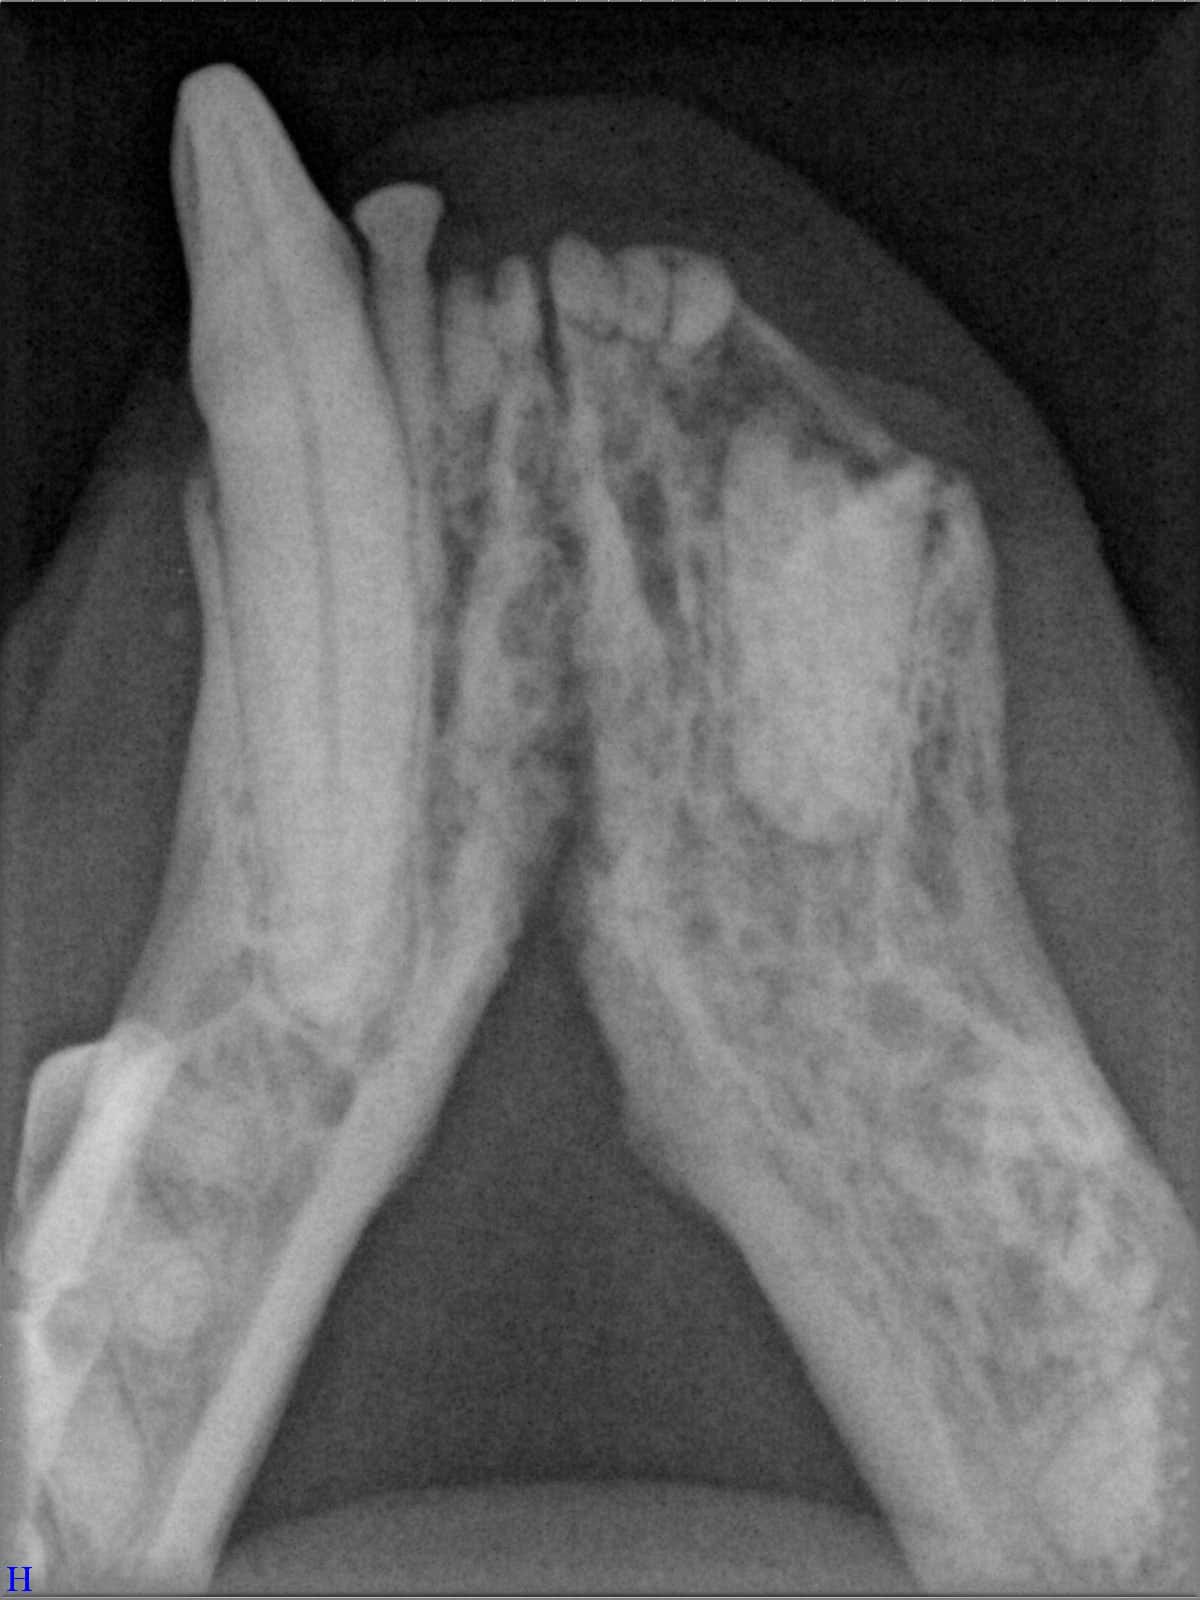

Ein entscheidender Baustein der FORL-Diagnostik ist das dentale Röntgen. Viele Läsionen sind von außen nicht sichtbar und lassen sich ausschließlich mithilfe moderner Röntgentechnik erkennen. In der Hamburger Praxis kommt digitales Dentalröntgen zum Einsatz, das detailreiche Aufnahmen bei geringer Strahlenbelastung ermöglicht. So kann FORL bereits in frühen Stadien diagnostiziert werden.

Das sehen Sie von außen – so sieht es auf den Röntgenbildern aus.

FORL Katze Röntgenbild

Röntgenbilder